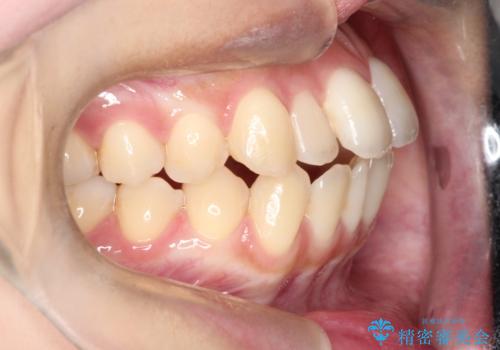

前歯のデコボコと突出を、目立たない矯正で解消

- 前歯のガタガタ(叢生)と、前歯が出ている(突出している)ことを気にされてご来院されました。精密な検査の結果、歯が並ぶスペースと、前歯を引っ込めるスペースの両方が不足していると診断。患者様のご希望に合わせ、透明で目立ちにくいインビザライン(マウスピース矯正)による治療計画を立案しました。スペースの確保は、奥歯全体を奥へ動かす遠心移動と、歯の側面をわずかに削る**IPR(歯間乳頭保護下ストリッピング)**を組み合わせて行い、前歯を効果的に引っ込めることを目指します。

今回の矯正治療では、透明なマウスピース型の装置インビザラインを使用しました。前歯を無理なく引っ込めるスペースを作るため、まず奥歯全体を後方へ移動させる遠心移動を実施。さらに、安全性が確保できる範囲で歯の側面をわずかに削るIPRを併用し、必要なスペースを確保しました。これらの処置により、前歯のデコボコが解消され、前に出ていた前歯も適切に引っ込みました。目立たない装置で治療を完結することで、叢生と突出感が解消され、機能性と審美性が向上した美しい口元を獲得していただけました。